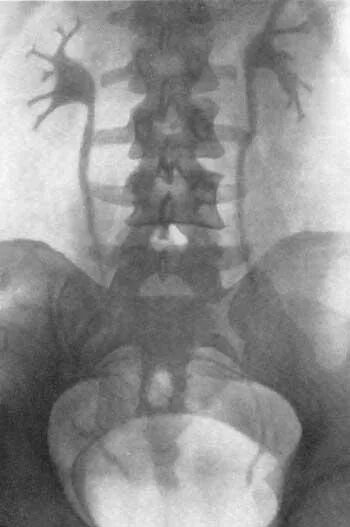

Урография с контрастом